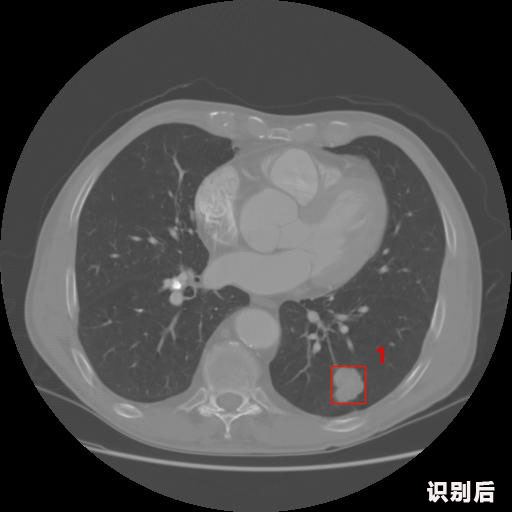

英特健康AI深度學習醫療圖像識別系統案例_胸部CT

1.發現肺結節的可能性為95.56%---位于框指數位置:[331.70554 366.13406 365.21707 403.96234]